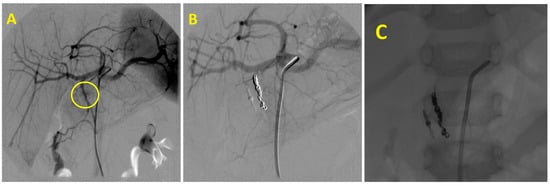

The embolization procedure can be facilitated by an endoscopically placed clip on the edge of a suspicious lesion. This helps the radiologist to target the local treatment of the bleeding area (Figure 2). Recent findings suggest the potential benefits of preventive embolization in bleeding duodenal ulcers in patients at significant risk of re-bleeding [20].

Figure 2. Gastroduodenal artery embolization in a patient with endoscopically untreatable duodenal ulcer bleeding: (A)—Duodenal wall hypervascularity (yellow circle). (B)—The final angiogram with the occlusion of the gastroduodenal artery. (C)—Embolic material–coils positioned next to the endoscopically placed clip, facilitating endovascular treatment and precise targeting.